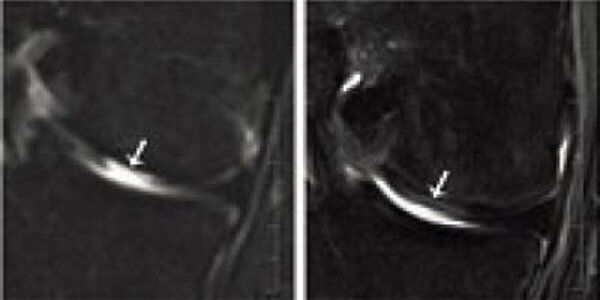

Nasal Septum Cells: From Nose To Knee, Engineered Cartilage Regenerates Joints

Human articular cartilage defects can be treated with nasal septum cells because they are able to adapt to the environment of the knee joint and can thus repair articular cartilage defects.  The nasal cartilage cells' ability to self-renew and adapt to the joint environment is associated with the expression of so-called HOX genes. The scientific journal Science Translational Medicine has published the research results together with the report of the first treated patients. Cartilage lesions in joints often appear in older people as a result of degenerative processes. However, they also…